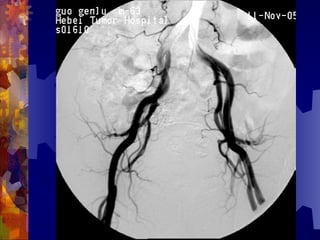

糖尿病足的检查

4. 足部 X- 线检查

5. 动脉造影(下肢)

男, 86 岁

双下肢多普勒血流图未探及血管

动脉造影血管闭塞